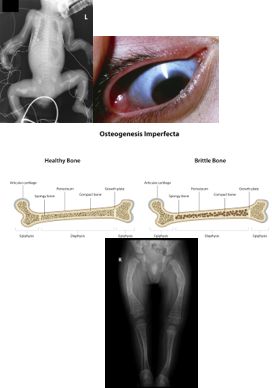

Osteogenesis Imperfecta

Genetic bone disorder with an autosomal dominant inheritance pattern that affects collagen type I production:

Low bone mass

Increased bone fragility

Connective tissue problems; unstable joints.

The estimated incidence is approximately 1 in every 12,000 to 15,000 births.

Occurs equally among males and females, and across races and ethnic groups.

Fractures may persist into adulthood.

Physical Characteristics:

**Blue sclera:

The most common ocular sign.

Caused by thin scleral collagen, allowing the underlying darker choroid vasculature to be seen.

Patients with OI show reduced thickness of corneal and scleral collagen fibers, resulting in low ocular rigidity.

Hearing loss

Frequent fractures

Short stature

Fragile dentition

Treatment:

Goal is to decrease fracture incidence and maintain mobility.

Bisphosphonate administration to promote bone growth.

Zebra lines are evidence of bisphosphonate treatment.

Physical therapy/occupational therapy to prevent contractures and maximize mobility.

Standing with bracing is encouraged.

Severe cases may require surgical insertion of rods into the long bones.

Lightweight splints or braces may allow the child to bear weight earlier.